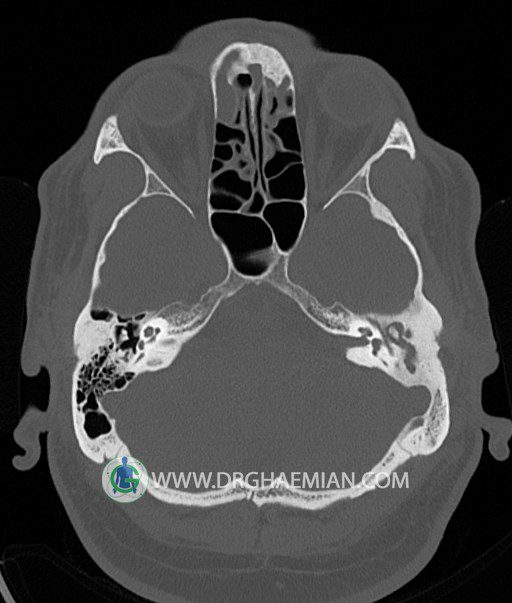

سی تی اسکن گوش داخلی به رادیولوژیست اجازه می دهد تا سطوح مختلف، یا اسلایس هایی از استخوان های که از جمجه به گوش می روند را از طریق امواج ایکس چرخشی مشاهده کند. در این کیس اودیت مدیا، ماستوئیدیت مزمن، اوتیت خارجی، انحراف سپتوم بینی، کونکا بولوزا و افزایش ضخامت سینوس ها مشاهده می شود.

در HRCT از استخوان تمپورال با مقاطع آگزيال ، ساژيتال و کرونال ظريف ( 0.6 mm ) :

– کانال عصب فاشيال و مسير ان از ناحيه کانال گوش داخلي ، geniculate ganglion تا محل خروج ان از stylomastoid foramen

– نماي tympanic membrane ، کانال ICA ، بولب جوگولار دو طرف

– انحراف سپتوم مياني بيني به راست

– کونکا بولوزا در کونکاي مياني چپ و

– افزايش ضخامت مخاطي در سينوس هاي اتموئيد و ماگزيلاري

اپاسيته